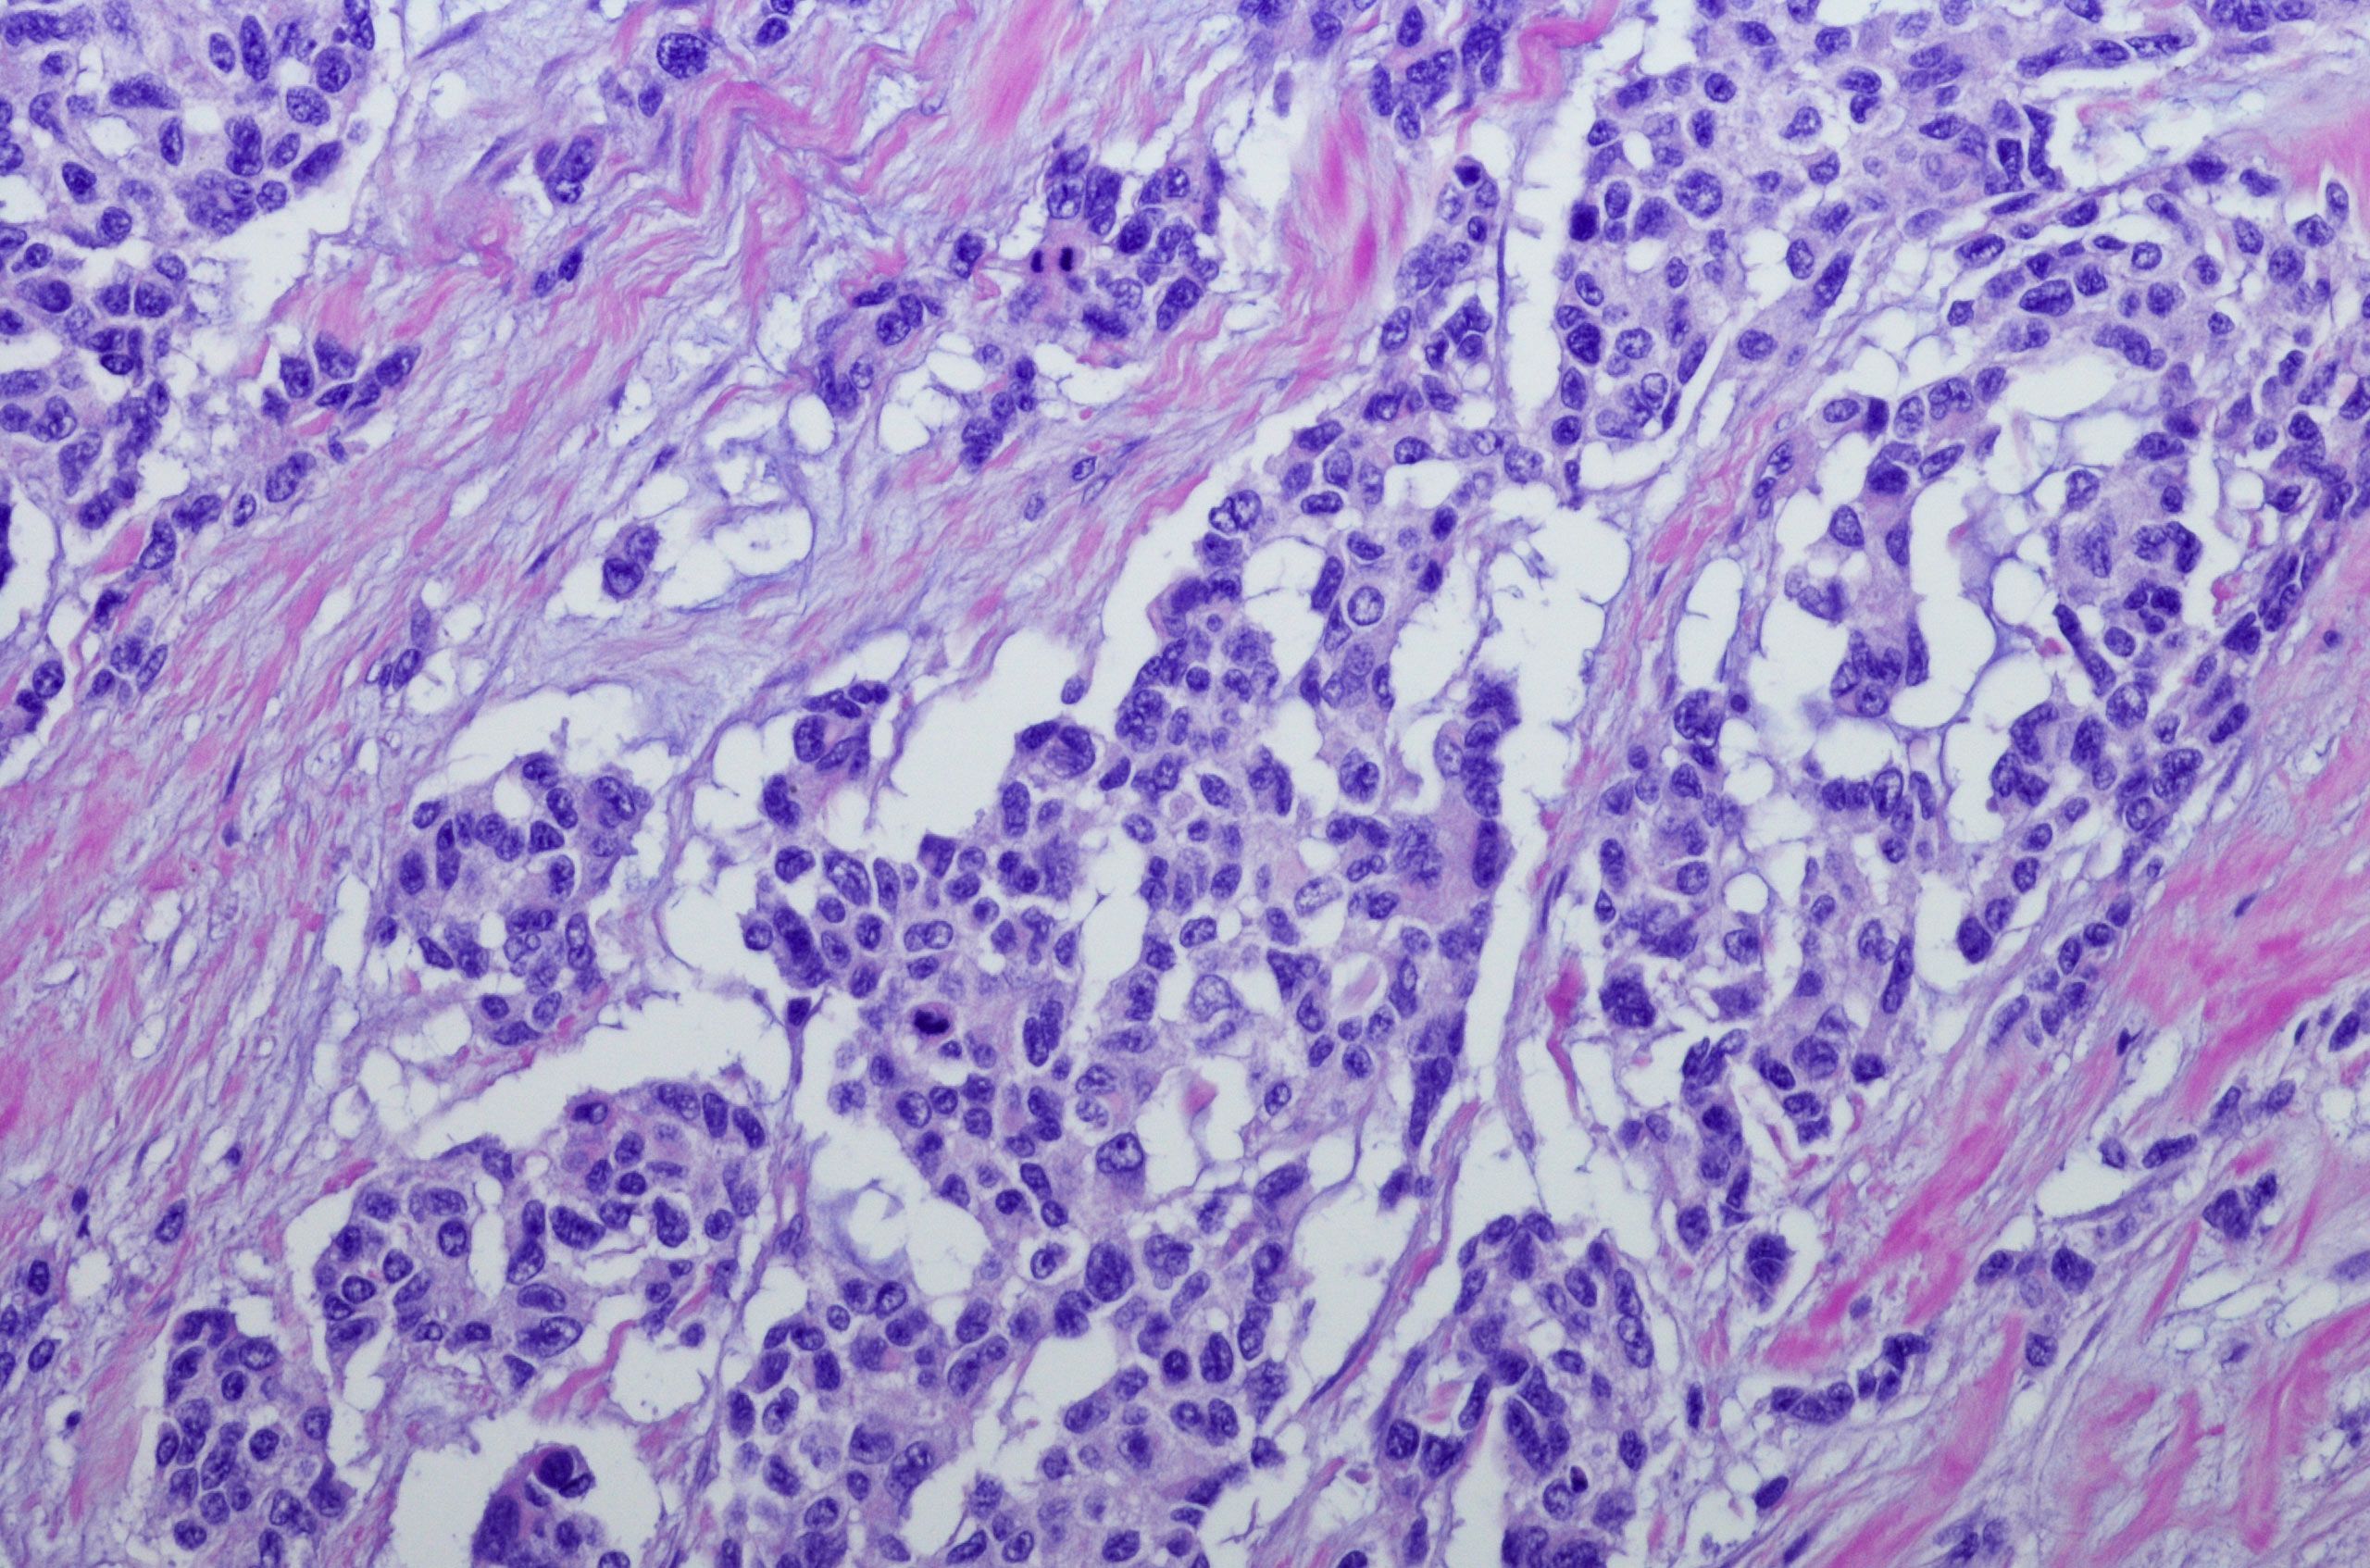

A large study published on June 24 in the Journal of Clinical Oncology has identified mutations in several genes that are associated with poor survival in children with a rare cancer that affects soft tissue called rhabdomyosarcoma, or RMS.

To find more genetic markers of RMS prognosis, the researchers sequenced tumor samples collected from two international cohorts of patients enrolled in clinical trials between 1998 and 2017. Using next-generation sequencing, they identified mutations, indels, gene deletions, and amplifications, and their associations with survival in 641 patients.